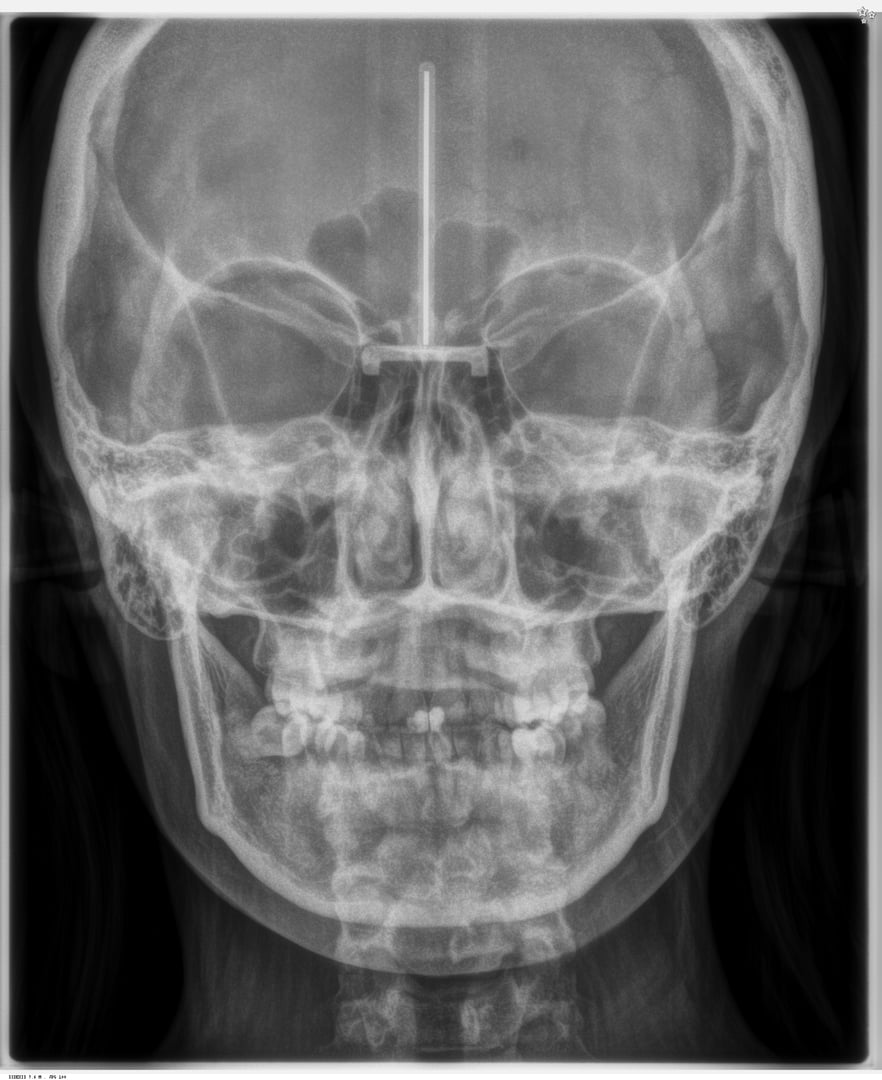

Radiografía PA de Cráneo

Es una herramienta esencial que te proporciona una visión clara y detallada de las estructuras óseas faciales y craneales. Te permite examinar simetría facial, alineación ósea y relaciones entre las estructuras dentales y esqueléticas con gran precisión. Ideal para el diagnóstico de maloclusiones, anomalías óseas y planificación quirúrgica